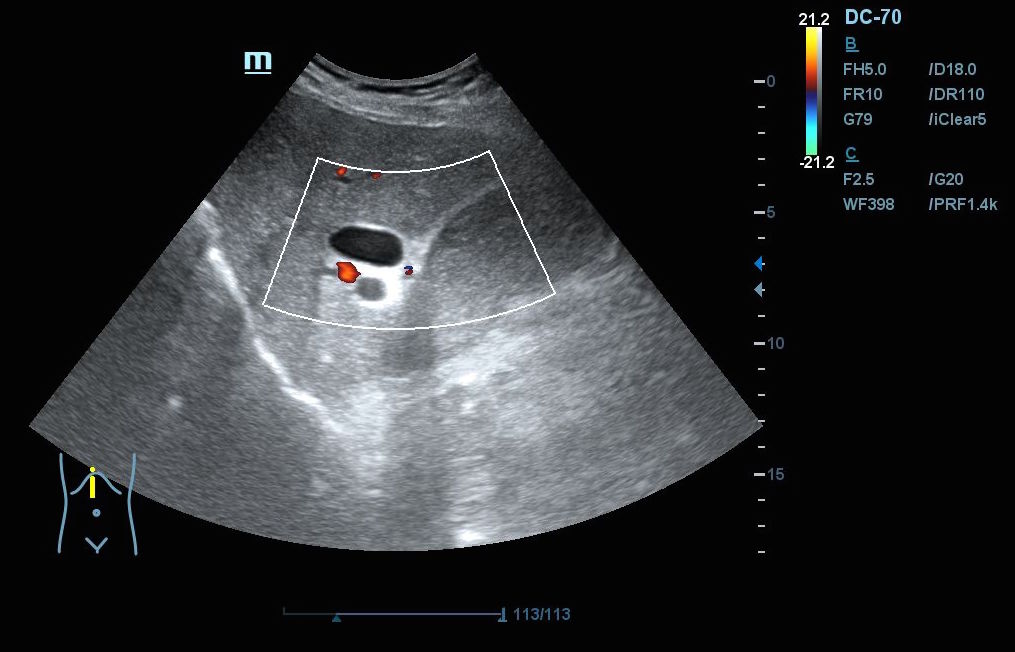

Hallazgos ecográficos: En el epigastrio se observa una imagen anecoica tubular, sin captación en Doppler, con un diámetro mayor a 2 cm, que sugiere una dilatación del colédoco (imagen 1). La vesícula biliar se encuentra completamente distendida y hepatizada, con una imagen en «doble cañón de escopeta» sugestiva de colestasis (imagen 2). En los cortes longitudinales se identifica una masa anterior a la aorta en el corte paramedial izquierdo, aparentemente localizada en el cuerpo del páncreas (imagen 3). En los cortes transversales se observa una masa que afecta tanto al cuerpo como a la cabeza del páncreas (imagen 4).